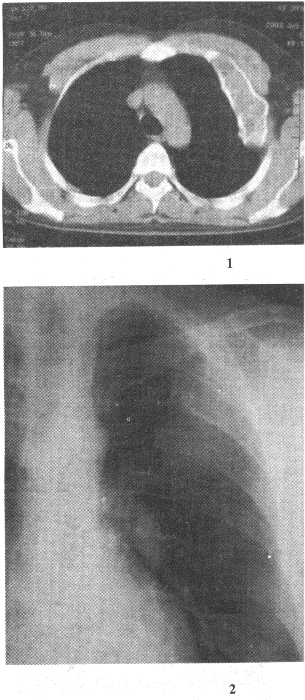

1.男性,50歲。涕中帶血絲1個月余,無發(fā)熱及咽部腫痛。CT檢查見圖所示,應(yīng)首先懷疑以下何種疾病

正確答案:A 解題思路:鼻咽癌病理上主要包括鱗狀細胞癌、腺癌、泡狀細胞癌和未分化癌。按其發(fā)展方向可分為上行型、下行型和混合型。

5.男性,40歲。查體發(fā)現(xiàn)肋骨病變,X線片和CT片如圖。應(yīng)首先考慮的診斷是

正確答案:D 解題思路:骨纖維異常增殖癥病理上正常骨組織被纖維組織或纖維骨樣組織取代,骨皮質(zhì)膨脹,邊緣硬化,病變內(nèi)可有嵴樣隆起。